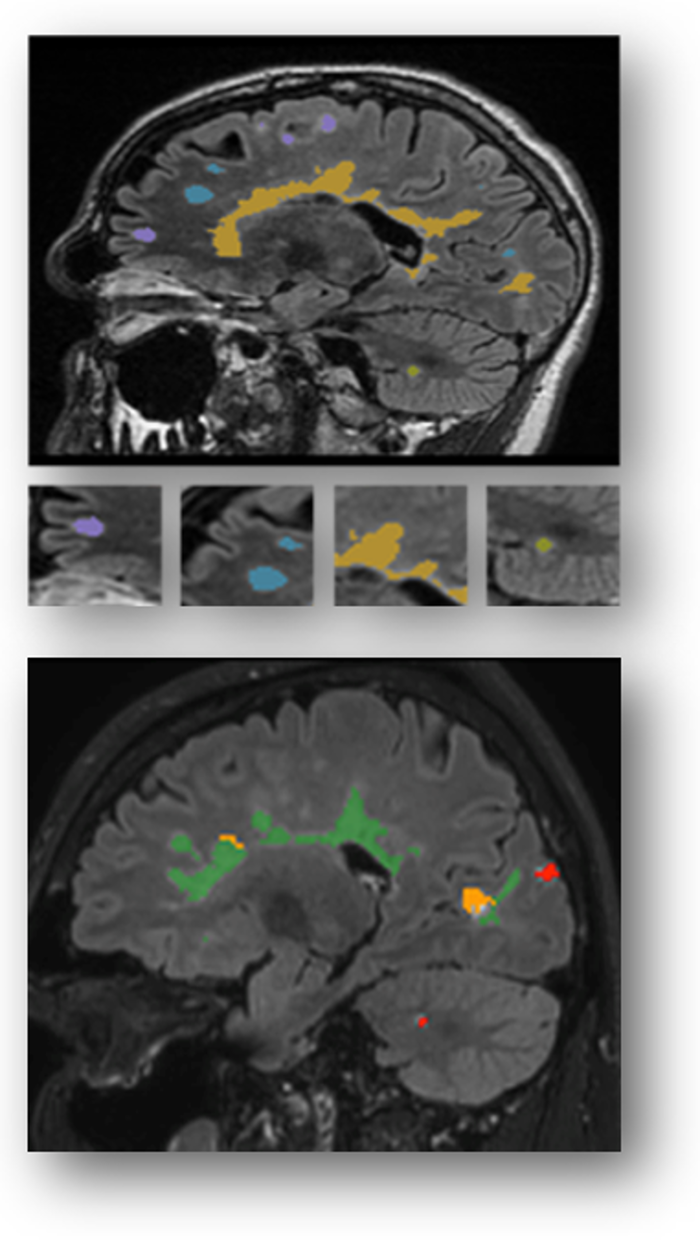

Lo studio mette insieme tre tipi di informazioni: i dati che arrivano dalla pratica clinica quotidiana, quelli raccolti in studi osservazionali e i risultati dei trial clinici. Il database, avviato lo scorso anno, sta crescendo rapidamente. Oggi include più di 55.000 risonanze magnetiche provenienti da oltre 7.500 persone con sclerosi multipla, accompagnate dai relativi dati clinici disponibili. Tutte le immagini MRI sono state analizzate in modo quantitativo dalla società icometrix, con sede in Belgio. Grazie a questa ricchezza di dati — che include anamnesi, terapie, ricadute, esami radiologici, imaging retinico (OCT), potenziali evocati e altri biomarcatori — sarà possibile sviluppare modelli AI in grado di prevedere con maggiore precisione l’evoluzione della malattia in ciascun paziente, individuare le terapie più efficaci e distinguere peggioramenti legati a ricadute infiammatorie da progressioni silenti.

Wim Van Hecke, Ceo di icometrix, ha aggiunto: «La risonanza magnetica è fondamentale per monitorare la progressione silente della sclerosi multipla. Il progetto Claims farà avanzare il settore grazie alla misurazione sia dei processi infiammatori sia della patologia “subdola” e persistente. Questo approccio innovativo è decisivo per consentire valutazioni guidate dai dati, offrendo ai pazienti le migliori possibilità di preservare la qualità di vita».